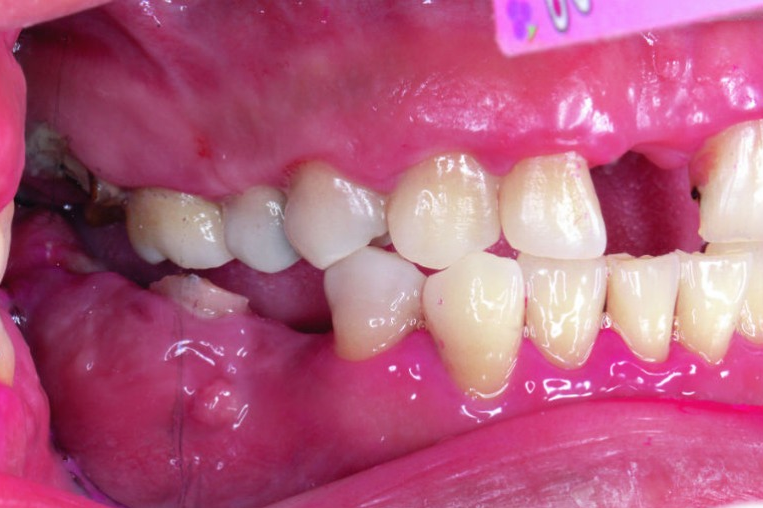

血糖控制不良,會加重牙周病, 沒有妥善治療牙周病,也會影響血糖,造成惡性循環。(圖片來源/新光醫院提供)